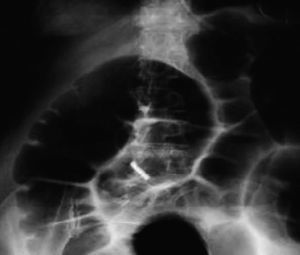

La paciente es nuevamente valorada a las 37h del parto persistiendo el mal estado general. A la exploración física presentaba taquipnea y aliento fecaloideo. El abdomen estaba distendido, timpánico con dolor difuso a la palpación con presencia de ruidos hidroaéreos. Asimismo la paciente refería deposición líquida. Se inicia tratamiento conservador mediante dieta absoluta, sonda nasogástrica, vesical, reposición hidroelectrolítica y neostigmina. La radiografía simple abdominal demostró dilatación del colon y distensión del ciego de 11cm compatible con POAC (fig. 1). Se realizó un enema hidropaco con el que se descartó la obstrucción mecánica. Luego de 40h y en vista de que las condiciones clínicas de la paciente continuaban iguales, se decide realizar laparotomía exploradora encontrando en cavidad abdominal 300ml de líquido fecaloideo y dilatación de segmento de sigmoides con signos de necrosis sin evidenciar obstrucción mecánica. Se realizó resección de parte del sigmoides y colostomía. La paciente evolucionó de forma satisfactoria y fue dada de alta 5 días después. Se realizó el cierre de la colostomía a los 60 días. El informe de anatomía patológica informó segmento de colon de 8 x 3cm, presentando a los 1 y 2cm de sus bordes de resección zona dilatada hasta 5cm, serosa pardo-grisácea con áreas violáceas, lisas. Al corte de la pared, zona dilatada, mucosa parda con ausencia de pliegues en área contigua a la zona afectada. No se reportó evidencia de neoplasia.